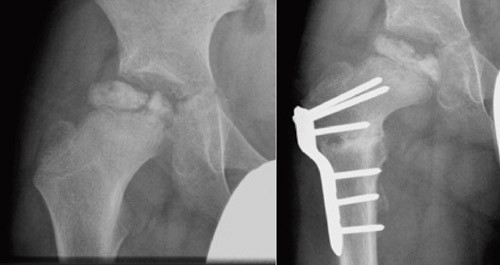

Ved femur- eller bekkenosteotomi sentreres caput femoris i acetabulum der det nekrotiske caput i fragmenterings- og gjenoppbyggingsfasen kan formes av acetabulum, slik at det blir mest mulig sfærisk ved tilheling (28, 29). Figur 4 viser et eksempel på en hofte ved Calvé-Legg-Perthes’ sykdom før og etter proksimal variserende femurosteotomi. Bekkenosteotomi synes å ha fått økende anvendelse internasjonalt. Flere studier har vist at denne behandlingen gir tilsvarende resultater som ved femurosteotomi (30, 31). Bekkenosteotomi utføres sjelden i Norge på denne indikasjonen og ble derfor ikke evaluert i den norske studien.